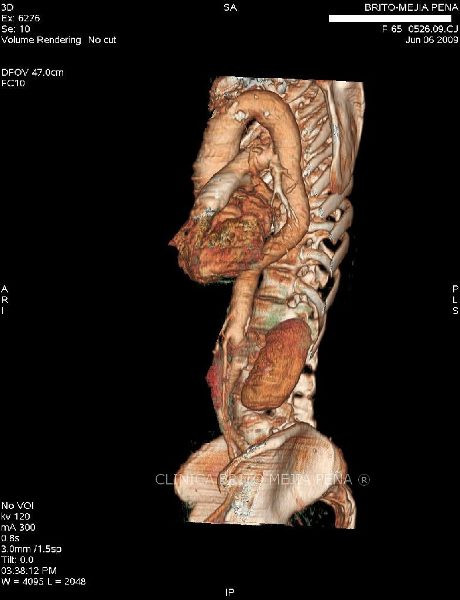

Hernia morgagni axial